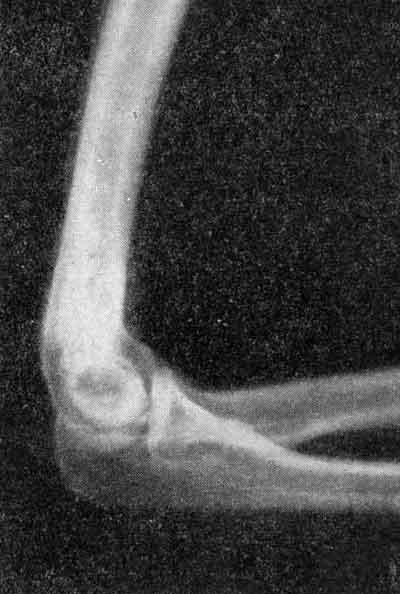

Рентгенограмма локтевого сустава.

Заметный остеопороз суставных отделов лучевой и локтевой костей.